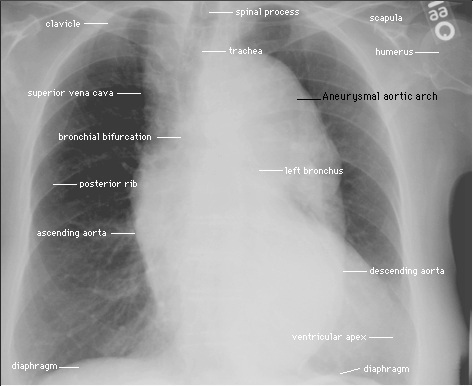

Radiografia del Torace: nelle proiezioni anteroposteriore e laterale che dimostrano uno slargamento dell’ombra mediastinica con evidente dilatazione aortica.